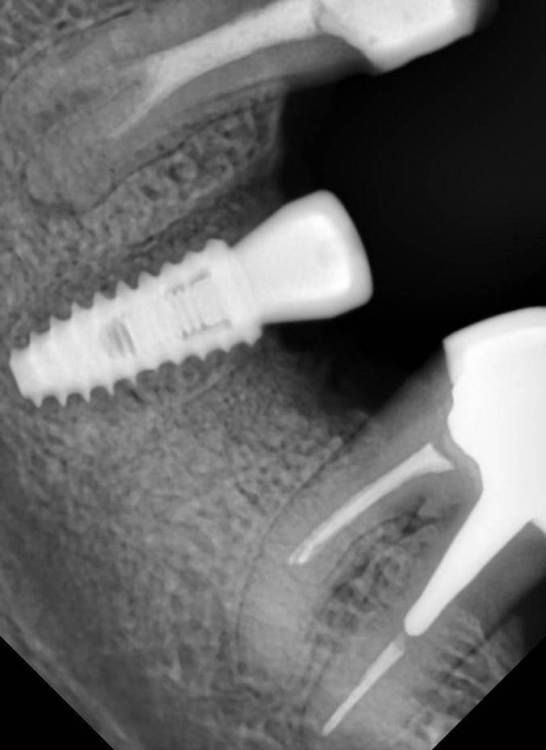

Jonik Опубликовано 6 февраля, 2022 Поделиться Опубликовано 6 февраля, 2022 Здравствуйте! Мне установили имплантат OSSTEM (TS IV SA) на место нижней шестерки. Я загуглил что за имплантат такой и на официальном сайте наткнулся на такую информацию - "Используется для установки в дистальном отделе верхней челюсти". Спросил у врача, который мне его и установил, все ли путем. Врач сказал что все в порядке, эти имплантаты подходят для моего типа кости (по-моему для мягкой кости). Подскажите все ли правильно мне сделали, имплантат подобран корректно? Ну и заодно оцените по снимкам хорошо ли установлен. Спасибо! Ссылка на комментарий

Женька Опубликовано 6 февраля, 2022 Поделиться Опубликовано 6 февраля, 2022 Здравствуйте. По данным снимкам всё хорошо. На самом деле нет никакой разницы. Практически все имплантаты сделаны из титана. Касаемо системы Osstem намного более важен диаметр имплантата в дистальном отделе челюстей. В вашем случае он выбран согласно рекомендациям производителя. Ссылка на комментарий

Irouil Опубликовано 6 февраля, 2022 Поделиться Опубликовано 6 февраля, 2022 (изменено) Все выглядит нормально Кроме соседнего зуба Изменено 6 февраля, 2022 пользователем Irouil Ссылка на комментарий

Doctor Vlad Опубликовано 6 февраля, 2022 Поделиться Опубликовано 6 февраля, 2022 все ок. ждем интегры Ссылка на комментарий

Irouil Опубликовано 6 февраля, 2022 Поделиться Опубликовано 6 февраля, 2022 @Jonik 5-го, который на снимке «слева», без вкладки По предоставленной рентгенограмме создаётся ощущение, что у верхушки корня присутствует воспаление. Если зуб не подвергался лечению в течении последних 12 месяцев - на него стоит обратить внимание Ссылка на комментарий